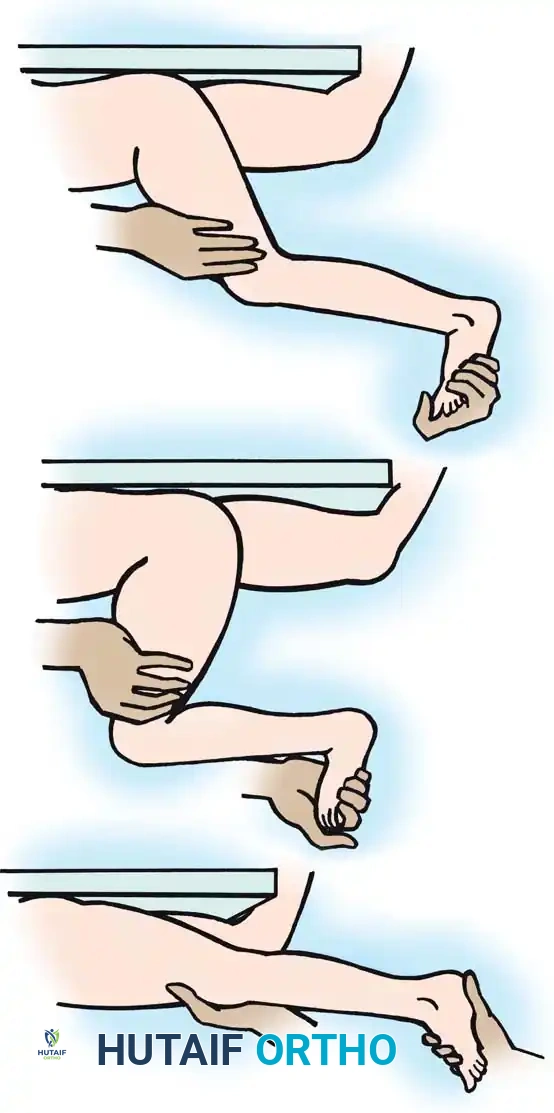

Gastrocnemius Assessment

The degree of ankle equinus must be measured with the knee both flexed and fully extended (the Silfverskiöld test principle). If ankle dorsiflexion significantly improves when the knee is flexed, the gastrocnemius (a two-joint muscle) is the primary source of spasticity or contracture.

Fig. 30-22 Testing for gastrocnemius contracture and spasticity. A, With knee extended, equinus in ankle is noted. B, With knee flexed, ankle is easily dorsiflexed, indicating no soleus contracture. C, As knee is extended, ankle dorsiflexion is resisted by tight or spastic gastrocnemius muscles.